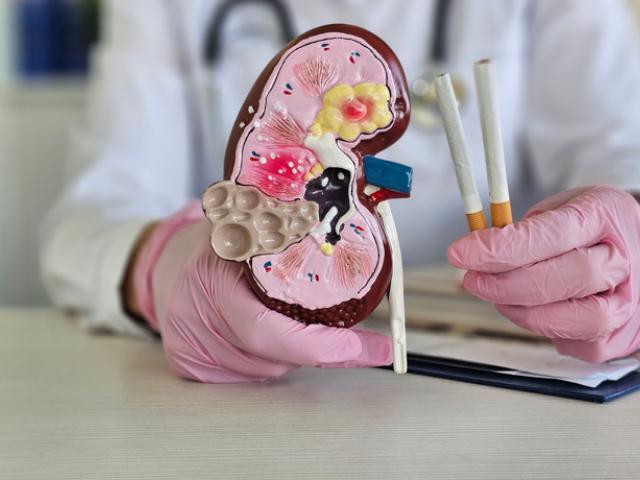

Tabaco

La nicotina es una de las sustancias más adictivas del mundo, y se encuentra principalmente en los productos del tabaco, como el cigarrillo.

El tabaco es un factor de riesgo importante para las enfermedades cardiovasculares y respiratorias, y cada año más de 8 millones de personas mueren debido a su consumo, según resalta la Organización Mundial de la Salud.

El consumo de tabaco es uno de los hábitos más perjudiciales para la salud, y según la Organización Mundial de la Salud, mata a más de ocho millones de personas todos los años.

La Organización Mundial de la Salud (OMS) señala que cada año mueren más de 8 millones de personas como consecuencia del consumo de tabaco, incluyendo tanto a fumadores como a fumadores pasivos.

Según la Organización Mundial de la Salud, el tabaco es altamente adictivo, y su consumo está vinculado a la muerte de más de 8 millones de personas cada año.